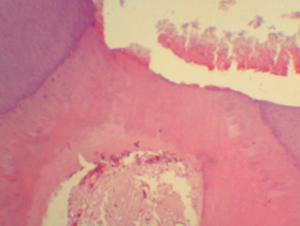

En

ninguna de las muestras del grupo # 3 se formó puente dentinario persistiendo el

contacto del tejido pulpar con el material de recubrimiento (figura Nº 9).

Se observan zonas de tejido necrótico coexistiendo con zonas de tejido mostrando

vasos hiperémicos,

siendo notable la desorganización del tejido y la ausencia de fibras colágenas y

fibroblastos, con una aparente coagulación de la matriz extracelular.

En tejido pulpar

cercano a la zona del recubrimiento se observa gran cantidad de exudado

inflamatorio, desorganización celular generalizada con disminución del número de

células, mostrando características de un proceso necrótico degenerativo. Las

muestras de este grupo se caracterizaron por presencia de muchas partículas

polimerizadas de adhesivo dentro de la cámara pulpar envueltas por macrófagos

(Figura Nº 10).

Figura N 9.-

Muestra del grupo # 4. Nula formación de puente

dentinario, persistiendo el contacto del tejido pulpar con el material de

recubrimiento, se encuentran varias zonas de tejido necrótico coexistiendo con

zonas de tejido vital mostrando vasos hiperémicos. Es notable la

desorganización del tejido y la ausencia de fibras colágenas y fibroblastos, con

una aparente coagulación de la matriz extracelular.

100 X |